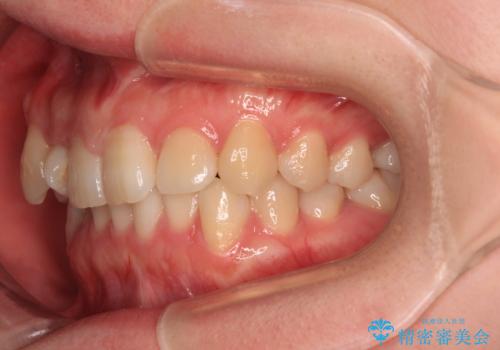

捻転の強い前歯 ワイヤー装置での非抜歯矯正

- 前歯のデコボコ、特に90度捻れている上顎前歯を気にして来院された患者様です。

捻転を解消する際に、歯列全体が前方に突出して出っ歯の仕上がりとなることが懸念されたため、補助装置を用いて上顎歯列全体を後方に移動する力をかけることとしました。

当初予定通り1年半ほどの治療期間で、非常に綺麗な歯列に仕上げることができました。